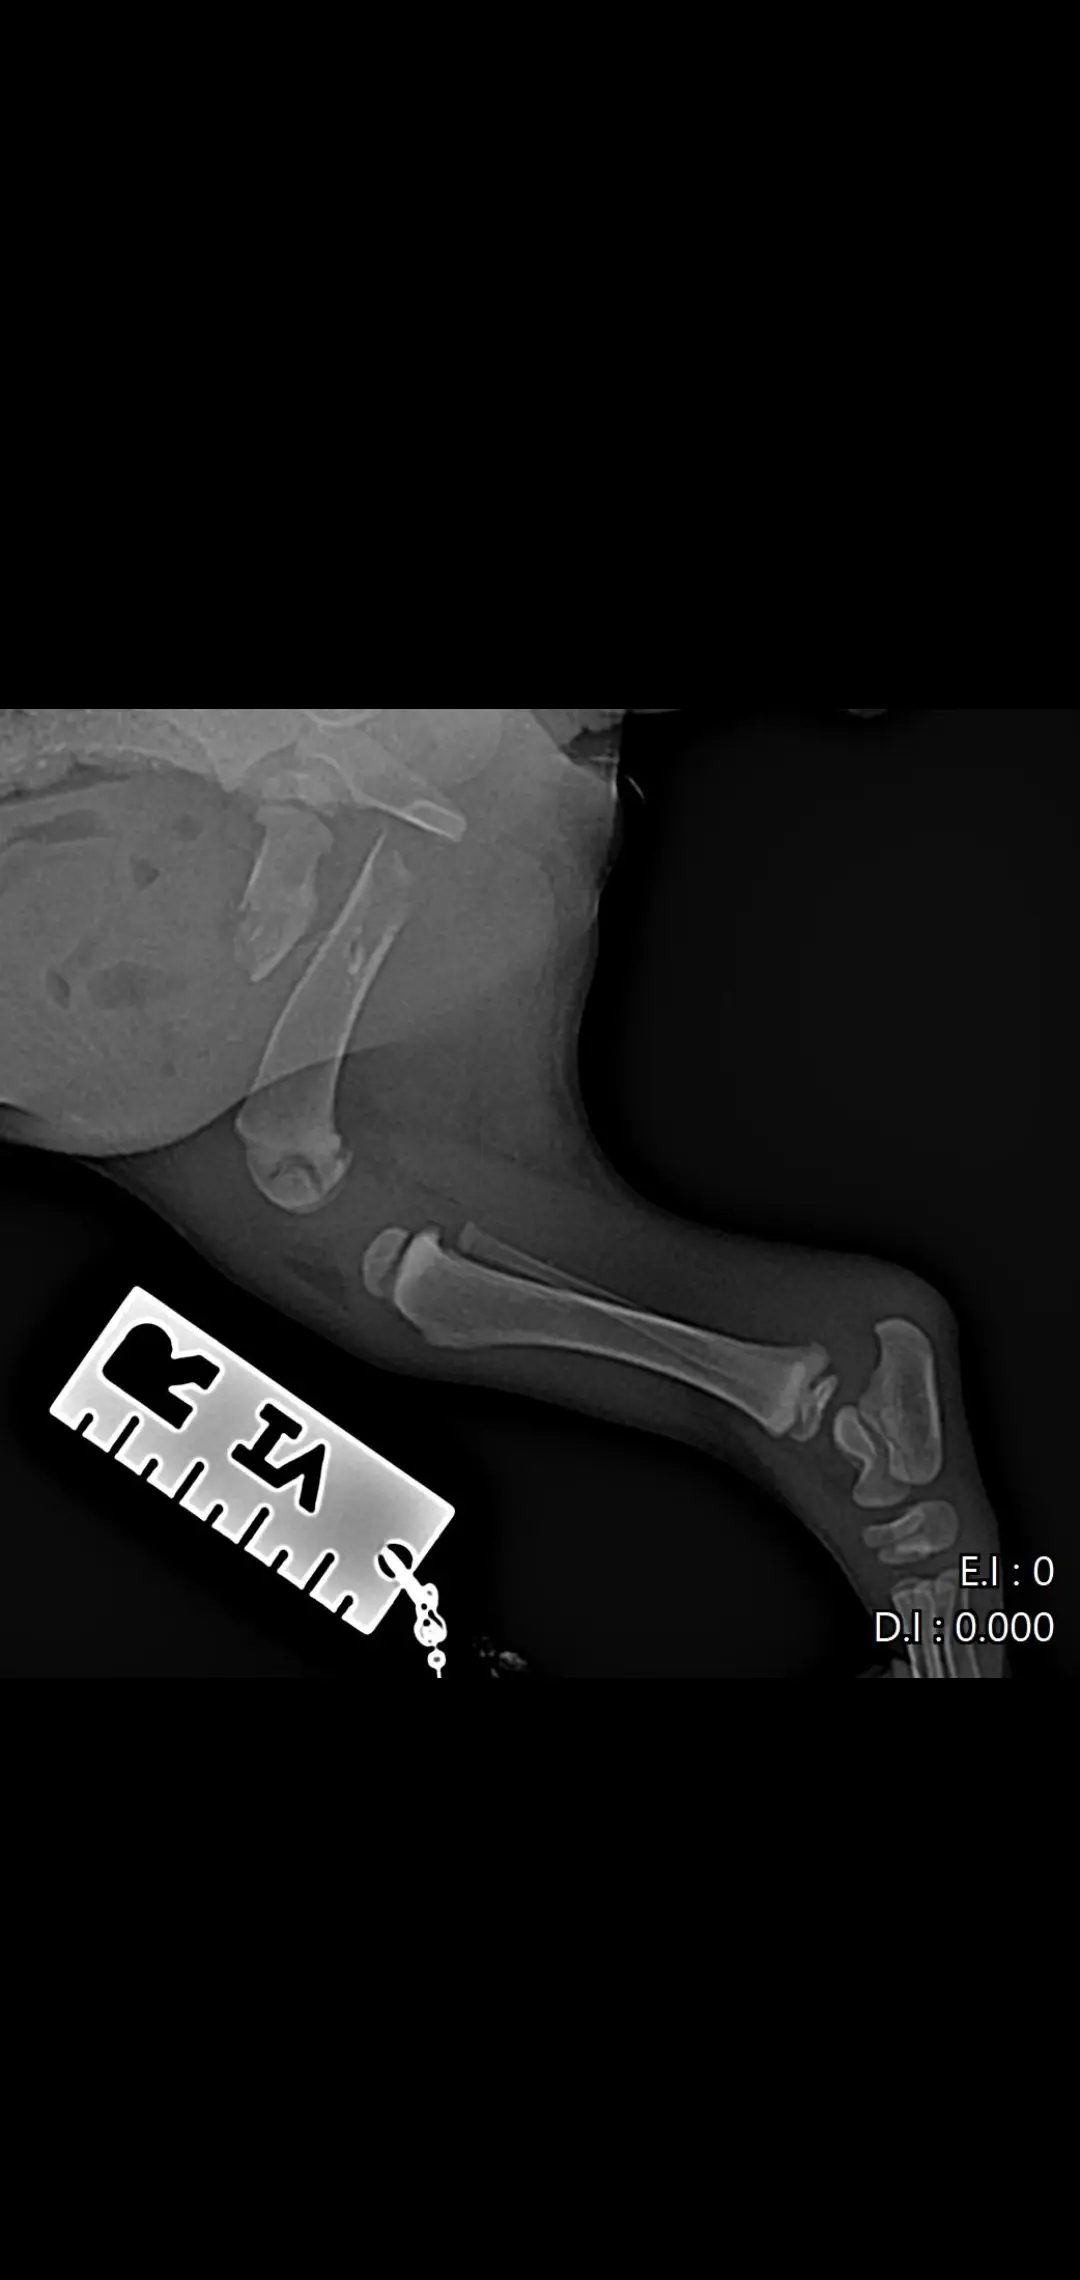

Намерих го в тежко състояние – със счупен таз и две счупени крачета. Не може да се движи, плаче при всяко докосване, но въпреки всичко се бори  да живее. 🐶😭

Бях с него във ветеринарна клиника „Провет“ в Пловдив (Тракия). Лекарят др Ташев го прегледа,оператор д-р Пачев (младши) ми каза, че има шанс да живее, но е нужна спешна операция и за двете крачета, която струва 1200 евро 😔

📸 Прилагам снимки от рентгена, за да видите колко тежко е състоянието му…плюс какво му беше изписано и направено в клиниката